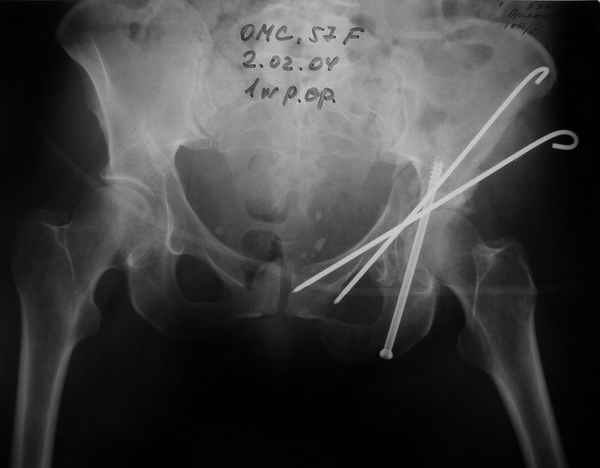

Женя! Класный перелом. Отлично репонируется изнутри таза, но лучше фиксированть сзади. Классический перелом для двустороннего доступа.

Однако есть альтернатива. Репозиция из подвздошного доступа тазовыми щипцами с разнодлинными браншами или тазовым пистолетом, а фиксация задней колонны через седалищный бугор или тазрвыми винтами 4,5 или каннюлированными 6,5 или 7,3. По-моему я посылал на ортофорум такой снимок, когда жаловался на ишемический неврит седалищного нерва через сутки после операции. Не забудь про шейку бедра - мне кажется будет хорош длинный PFN любой фирмы, какую ты найдешь, а нет так UFN + miss a nail, как это здорово делают мои земляки - Ебурбуки. Пока.

02.02.04